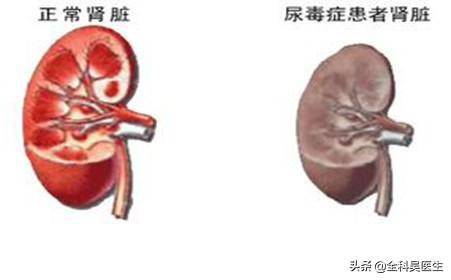

La néphropathie hypertensive, si on ne la surveille pas et si on la laisse évoluer, finit par se transformer en urémie. La glomérulonéphrite primaire, la néphropathie diabétique et la néphropathie hypertensive sont les trois principales causes d'urémie dans notre pays.

L'hypertension à long terme, si elle n'est pas contrôlée, peut conduire à l'athérosclérose des petites artères rénales, à l'hypoplasie rénale, à l'hypoplasie rénale, à une nouvelle augmentation de la pression artérielle, ce qui entraîne un cercle vicieux, et finalement, la fonction rénale continue à se détériorer, devenant une urémie.

L'hypertension artérielle peut également entraîner une atrophie des reins.

Les reins normaux sont ronds et pleins, et l'hypertension artérielle à long terme entraîne un rétrécissement des reins des patients, avec une surface granuleuse et une diminution de la fonction rénale.